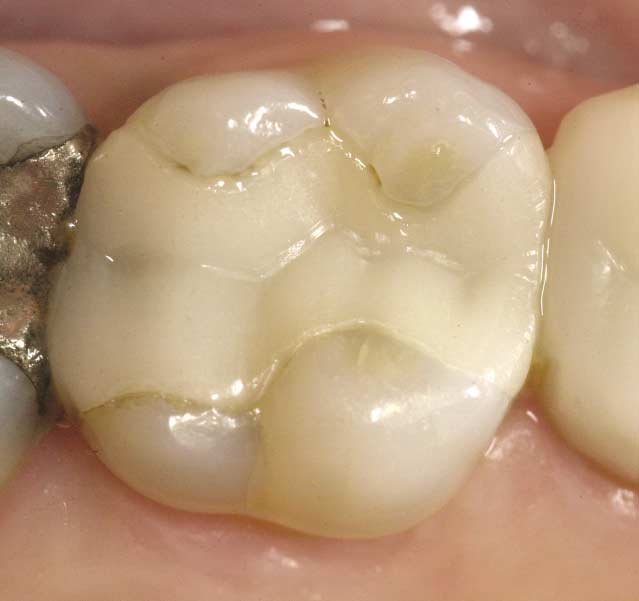

위 인레이를 보세요. 경계부가 다 보입니다. 저 인레이의 경우에도 원래는 티가 안났을겁니다. 인레이와 치아의 경계가요. 그런데 시간이 지날수록 미세한 틈에 음식물이나 치태가 쌓이게 되어 변색이 일어난 것입니다. (출처: https://www.researchgate.net/)